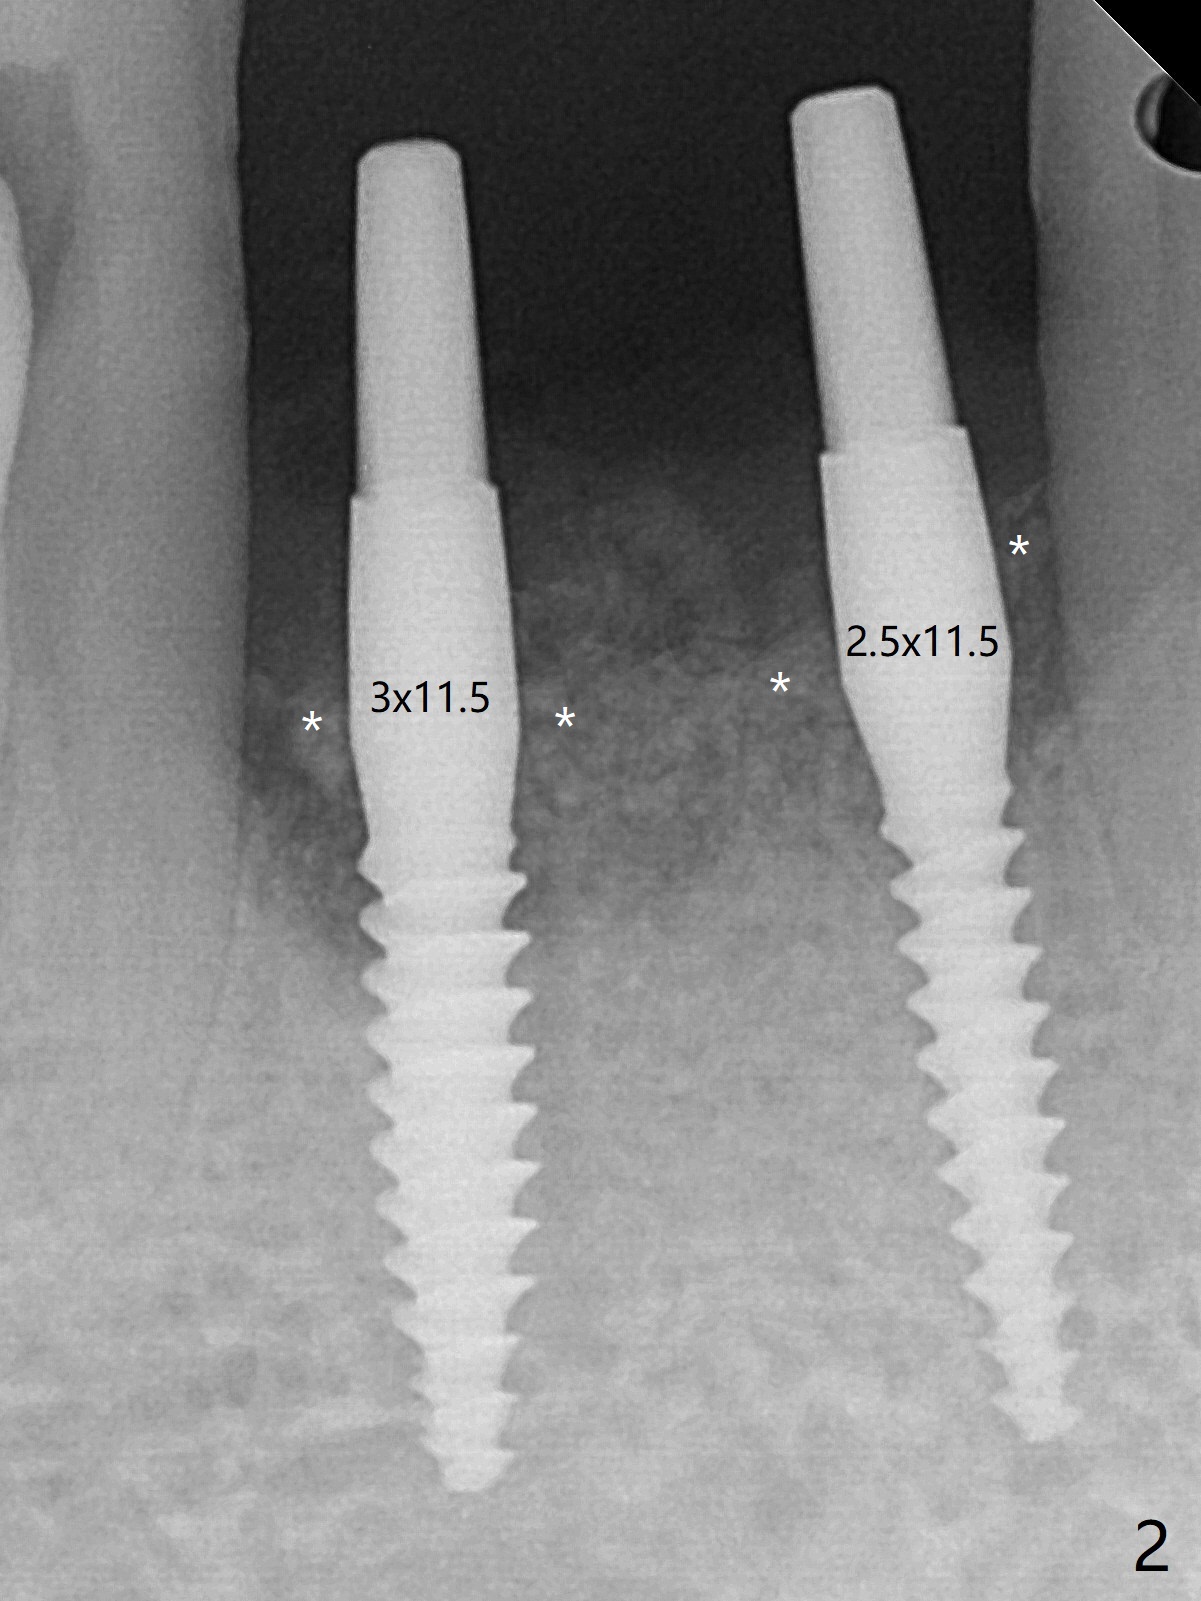

After placement of implant at #30 with high torque, osteotomy is prepared with 2.2 mm drill at #24 (M) first (Fig.1 before flap surgery). A 2.5 mm mini implant is placed < 10 Ncm (Fig.2,3). Since the ridge at #26 is apparently wider than that of #24 (Fig.1), a 3x11.5 mm implant is placed after the same drill (2.2 mm); insertion torque is ~ 35 Ncm. Bone graft is placed around the implants (Fig.2,3 *) before placement of PRF membrane. The patient is unpleased with our being unable to fabricate an immediate provisional (because of low torque at #24) as we have promised to. He is going to attend a wedding in fortnight. Instead periodontal dressing is applied. The latter is slight loose 1 week postop (Fig.4). There is apparently no bone loss 4 months postop with ~ 3 month provisional (Fig.5). The gingiva is healthy in spite of poor oral hygiene.